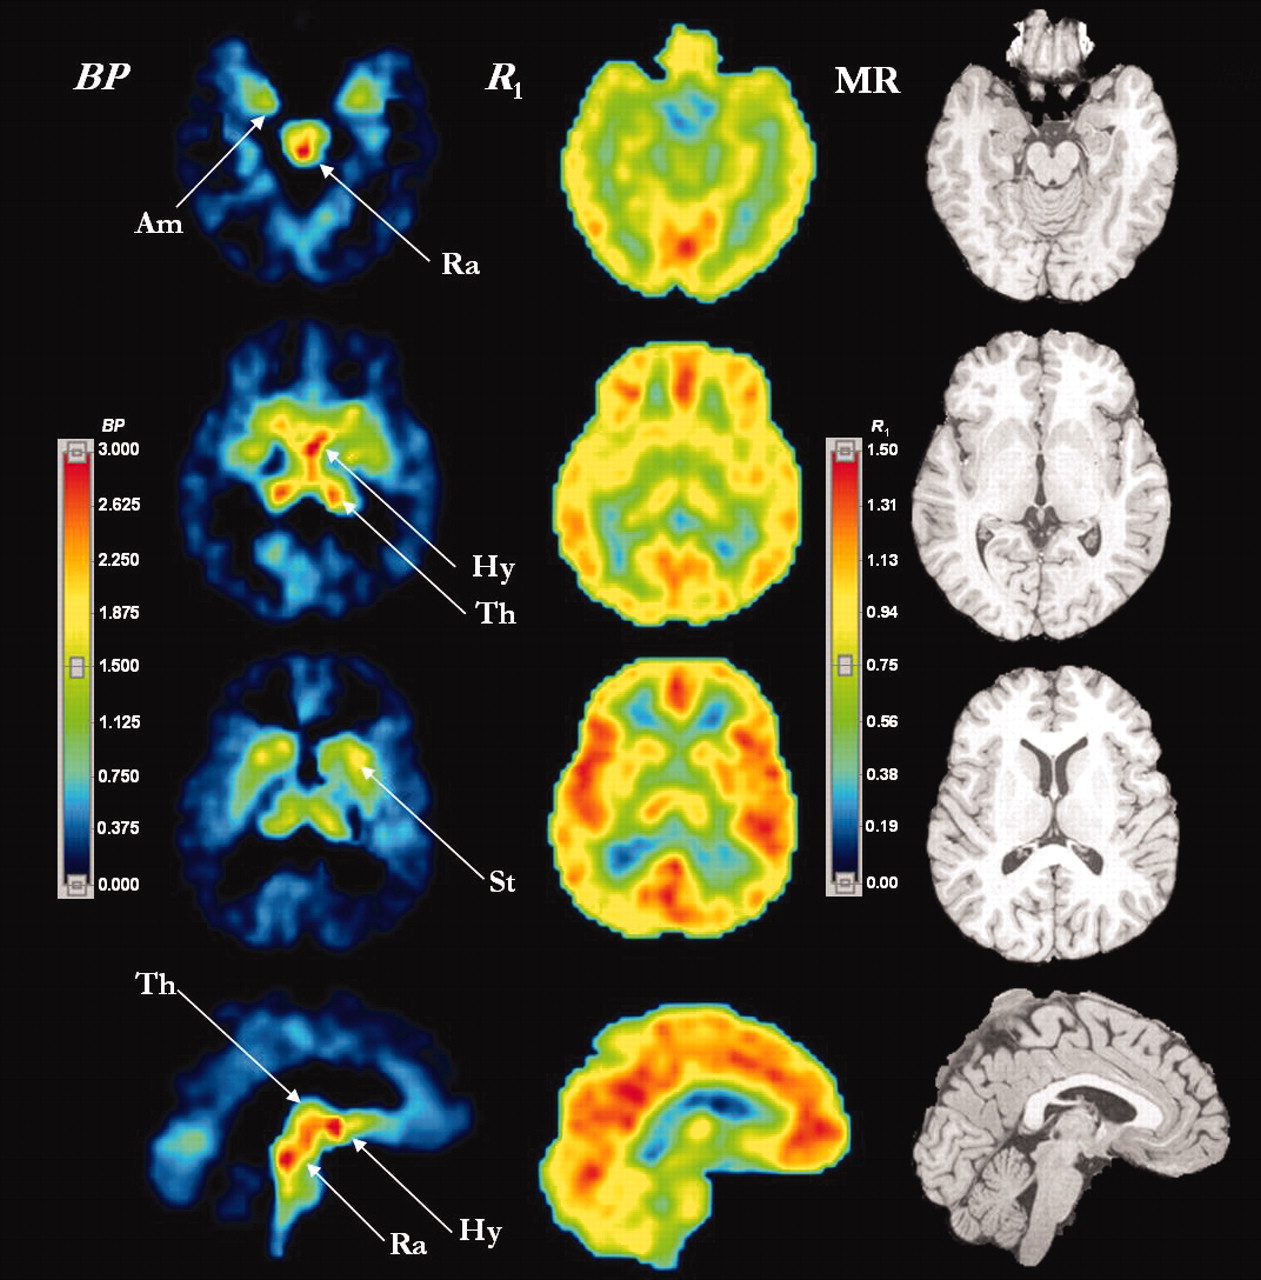

Using imaging techniques to identify the location of SERT. Positron emission tomography of SERT, showing parametric images of [11C]-DASB binding potential (BP) (left column) and relative delivery (R1) (middle column) estimated by the two-parameter multilinear reference tissue model, MRTM2. MRTM2 is a data analysis method that allows “volume pixel” (i.e., “voxel”)-wise mapping of SERT density (BP) and relative blood flow (R1) from dynamic [11C]-DASB PET data. (Voxelization is a process whereby the addition of depth to an image is gained by using a set of cross-sectional images.) Magnetic resonance (MR) images (right column) are shown for comparison. Upper rows are transverse images and the bottom row presents sagittal images. The color display ranges for BP images are 0 to 3.0 and for R1 images are 0 to 1.50 with higher numbers indicating greater SERT density (BP) or greater relative blood flow (R1) reveal where SERT may be more highly concentrated in brain areas. Am, amygdala; Hy, hypothalamus; Ra, raphe complex; St, striatum; and Th, thalamus. This figure was kindly provided by Drs. M. Ichise and R. Innis (64).